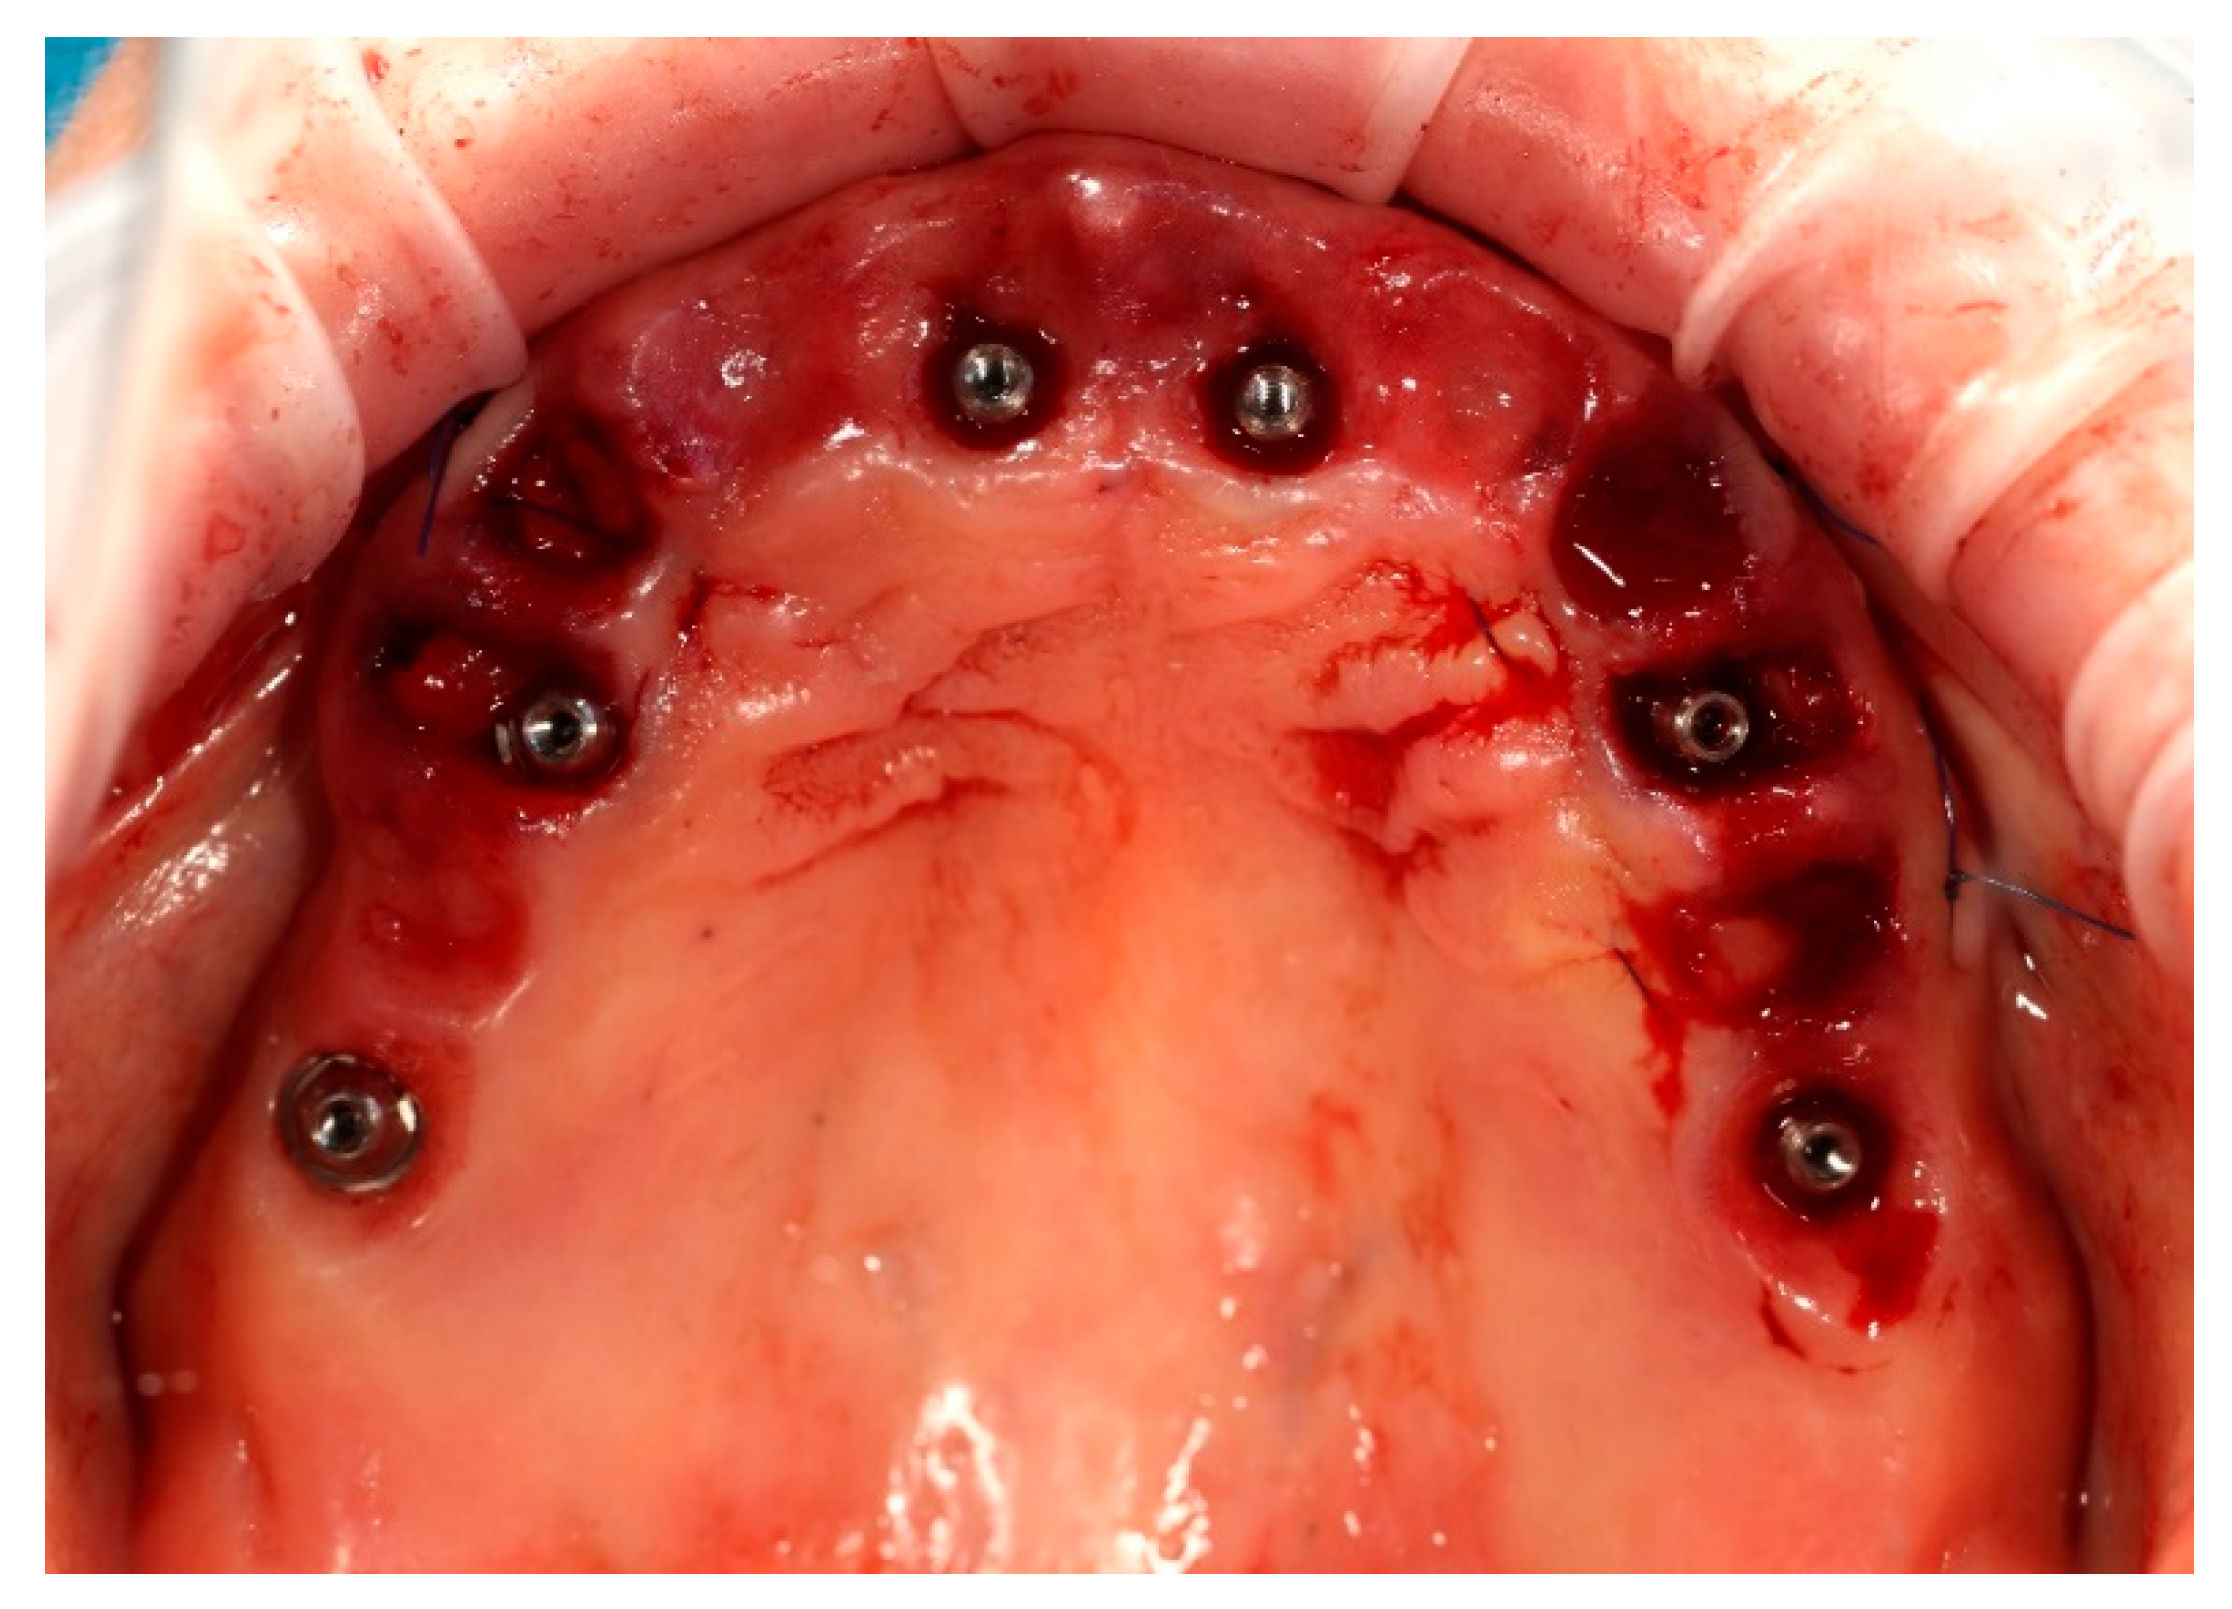

Simultaneously, the existing implant-supported crowns in positions 16 and 26, as well as the anterior implant-supported bridge, were unscrewed from the supporting implants. Multi-unit abutments were then selected and secured onto all six supporting implants, including the newly placed implants at sites 14 and 24 (Figure 4).

Figure 4. Multi-unit abutments secured onto all six supporting implants, including the newly placed implants at positions 14 and 24, following removal of the existing restorations.